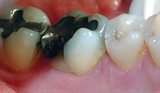

Bildet viser en jeksel i underkjeven med en stor amalgamfylling. Det går en tydelig bruddlinje langs den ene tyggeknuten.

![]()

Bruddlinjen førte over tid til at tannen frakturerte.